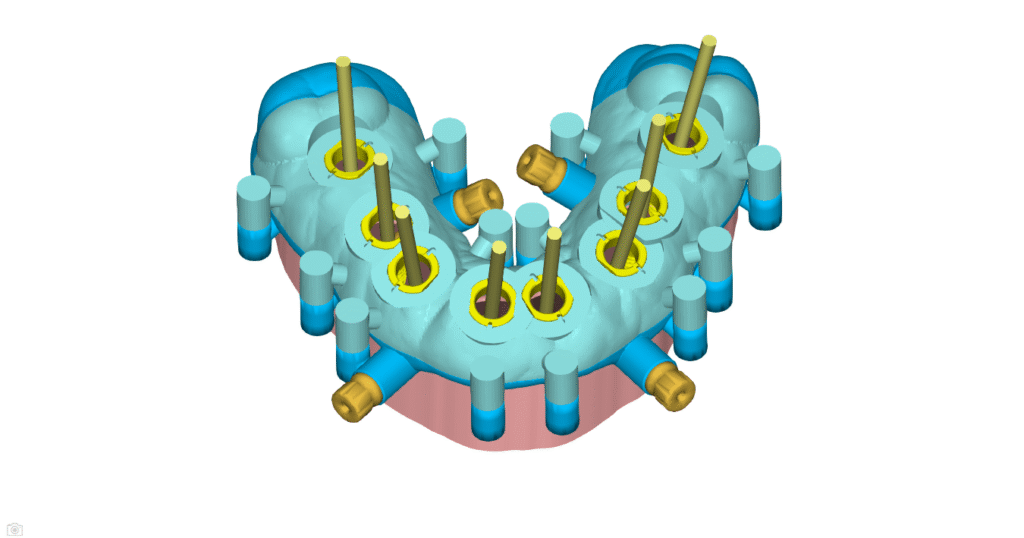

Implant Planning & Surgical Guides

Guided surgery is fast becoming the standard of care in the modern world.

Allow us to perfectly plan your implant case, based on years of experience from single unit to full arch cases.

We use NemoScan Implant Planning Software from Nemotec- SPAIN, a Henry Schein Company. NemoScan is the worlds most advanced implant planning software that gives us abilities that no other software on the market gives.

Stackable Guide

These guides are used for full-arch FP1 and FP3 cases and can be gingiva-supported or bone-supported. These cases are complex and typically performed by Dental Specialists. We use JB Dental Lab in the USA for the design and manufacture of the final prosthesis, but we can manufacture the temporary prosthesis locally. Feel free to use your preferred lab.